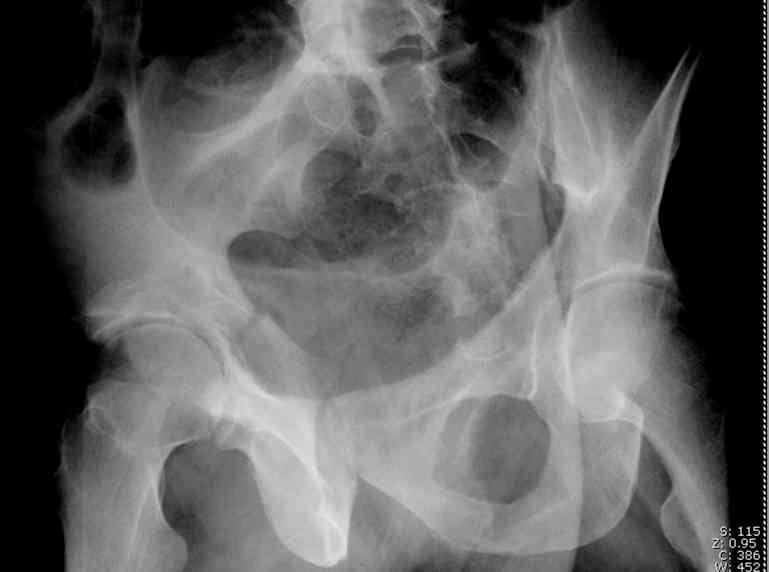

the case that I found is a 20yo male, MCC. his AP pelvis shows an interesting position of his bladder. it is pushed aside by a hematoma from SGA injury. we did a limited lateral window approach for the anterior column first, pt bumped up/supine. then closed and repositioned for KL. I could not find intra-op photos of cases when we did only a small incision for the AC screw (but they do exist!!). the lateral window is available for reduction assessment if a KL approach is being used. in the lateral position this window is available. the prone position definitely takes pressure off of the post column and facilitates reduction. in the lateral position a schantz pin in the ischial tub +/- bone hook in sciatic notch helps with PC reduction. the lateral position also gives better airway access for anesthesia. airway problems are rare, but prone position seems to be a bit more of a challenge to exchange the tube, or reintubate altogether. just something further to debate!